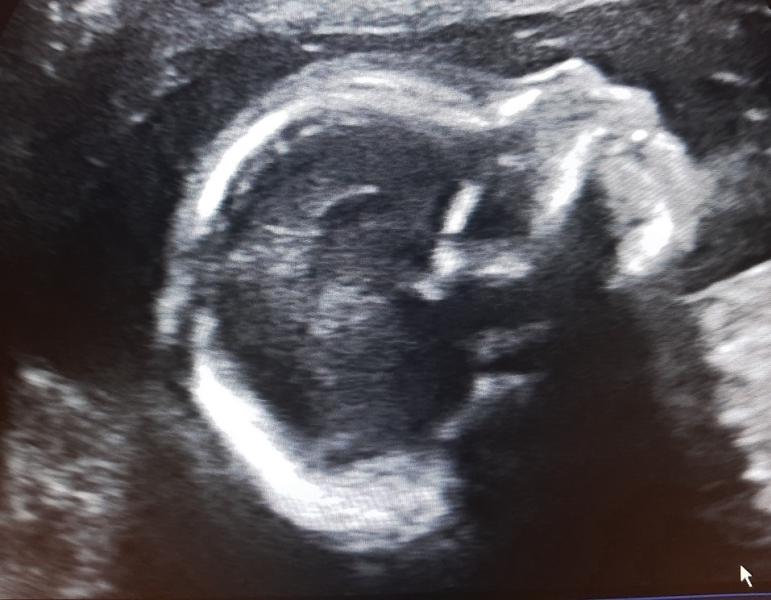

5 лет мы ждали этого парня🥰